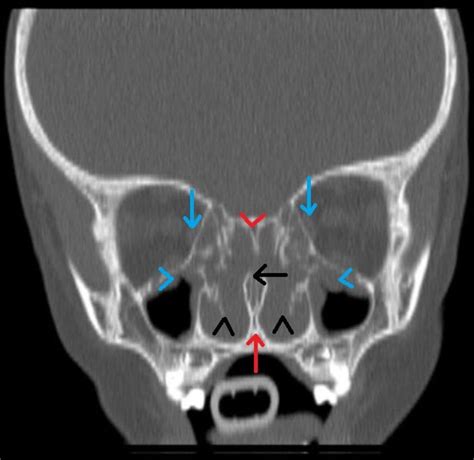

To understand why these structures become a problem, it is first necessary to understand what they are. Nasal turbinates, also known as nasal conchae, are shelf-like structures made of bone covered in soft tissue and mucous membranes that line the inside of your nose. You have three pairs of these—superior, middle, and inferior—on both sides of your nasal cavity.

Diagnosing inflamed nasal turbinates typically involves a physical examination by an ENT doctor using a small, lighted instrument called an endoscope. This allows the doctor to look deep into the nasal cavity to see the extent of the inflammation and ensure there are no other structural issues, such as a deviated septum or nasal polyps.